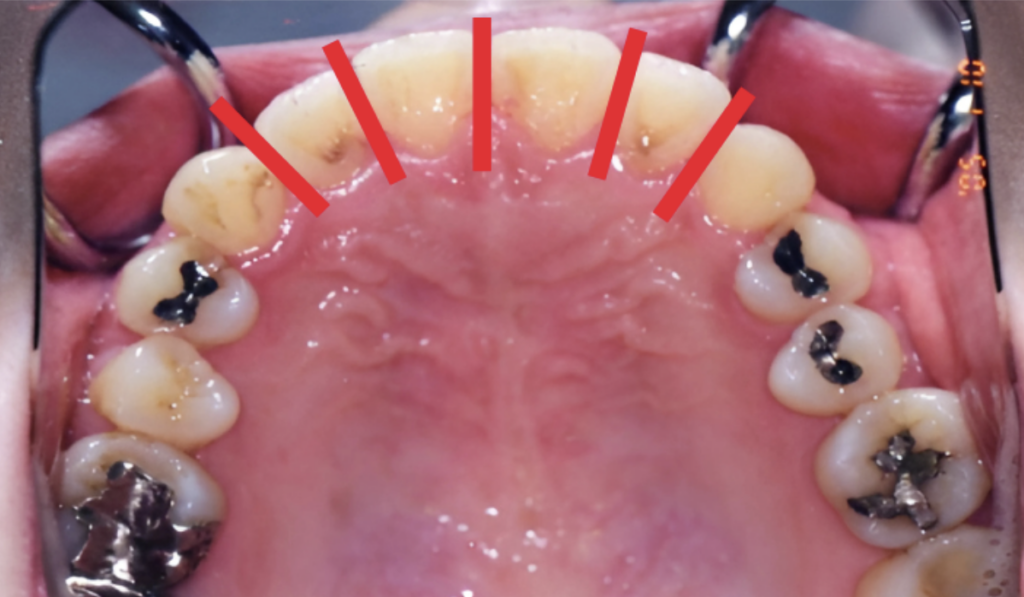

「拡大」は、歯並びのアーチ全体を横方向や前方向に外側に押し出すことで、歯列のサイズを大きくし、スペースを作る方法です。

歯のアーチはV字状になっているため、1ミリ外側に押し出すことで、実際には2ミリ程度のスペースを生み出すことができます。さらに2ミリ程度外側に押し出せば、4〜5ミリのスペースができる計算になります。

大人の場合、顎の骨はもう動きません。大人の非抜歯矯正で可能となるのは、「歯列だけの拡大」です。

これは、歯が植わっている骨(歯茎の骨:歯槽骨)の範囲内で、歯を少し外側に傾けたり、角度を変えたりすることでスペースを作る方法です。

しかし、この拡大には明確な限界があります。